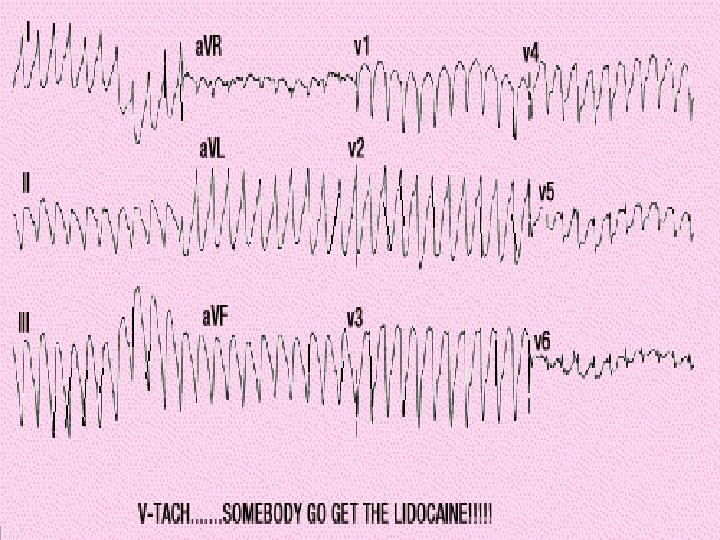

Conduction • Occurs approximately every 0. 8 seconds. • Electrical impulse can be recorded on an EKG • Used to detect abnormal activity or disease.